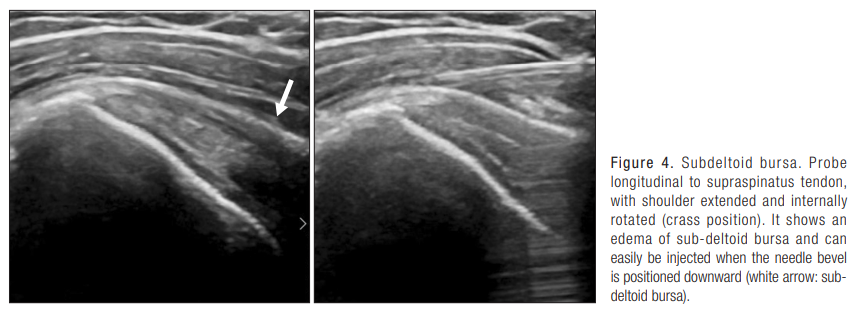

2. 견봉하 점액낭 주사( Subacromial subdeltoid bursa injection)

점액낭은 견봉의 하부, 대결절의 상부에 위치, 삼각근 바로 밑에 존재

-> subdeltoid라 칭하는 이유

검사 자세: 견관절을 내회전 및 신전 상태로 유지(Crass position)

-> 극상건과 동일.

초음파 영상

위의 초음파 사진에서는 2층의 고 에코성(밝은)의 선을 peribursal fat layer라고 하고, 그 사이의 저 에코성(어두운)의 부위를 subdeltoid bursa라고 한다. 통상적으로는 2mm 이내의 두께를 갖고, 그 이상이면 점액낭염(bursitis)라고 함.

주사 시에는 bevel의 위치를 아래로 향하게 하고, 주사액을 주입.

국소마취와 스테로이드를 병합한 약물을 사용.

초음파를 사용하면, 적은 용량의 스테로이드를 사용할 수 있어서 주변 조직의 손상을 최소화

peribursal fat layer 사이에 needle을 위치시키고, 주사액을 주입하면 저항없이 layer가 벌어지는 것을 확인할 수 있다

이런 경우 주사액이 정확한 위치에 들어가고 있음을 의미.

Needle의 끝이 deltoid의 muscle layer나 supraspinatus tendon 내에 위치하면, steroid에 의한 손상을 초래할 수 있다.